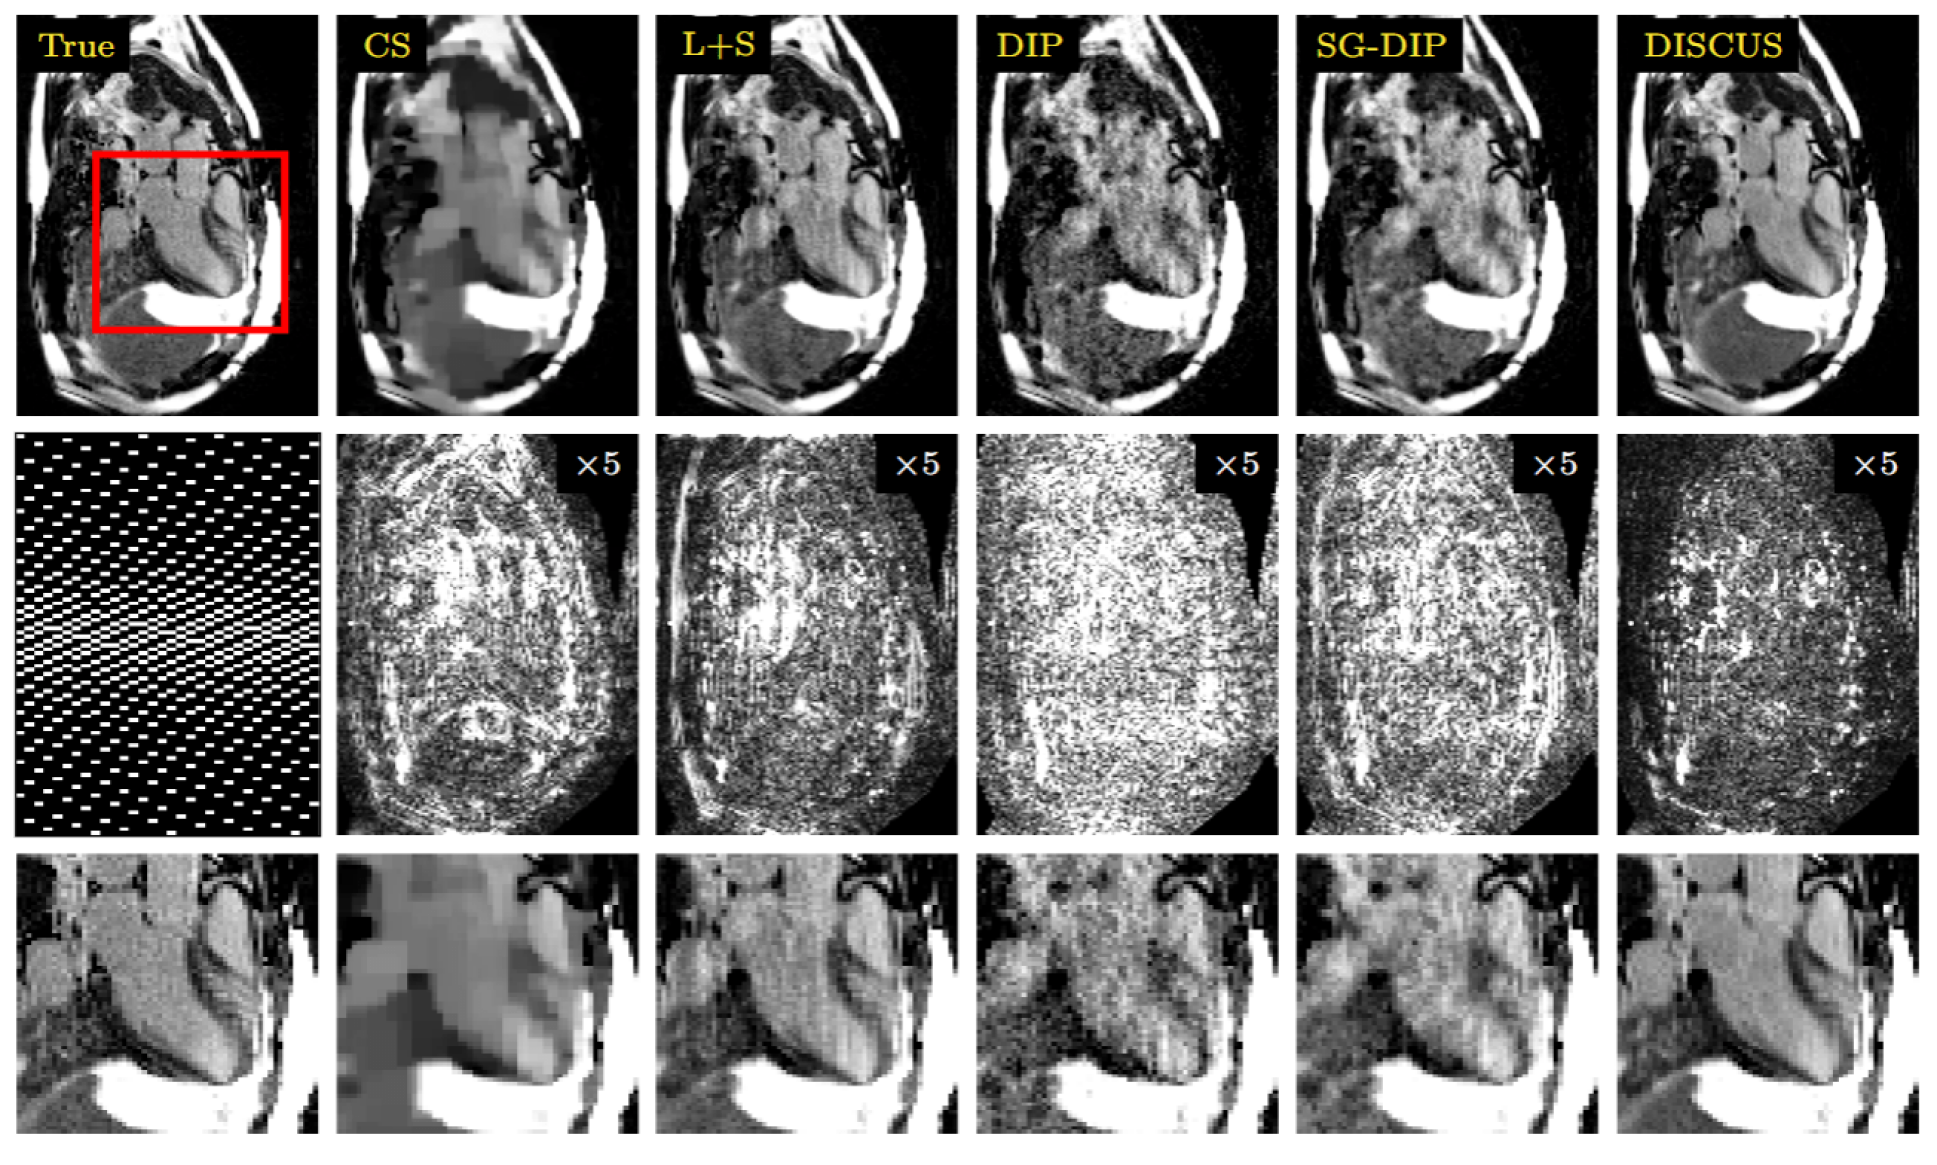

Refer to caption

Figure 3: Representative results from the simulated LGE (Study II) exhibiting a pronounced myocardial scar at R=4𝑅4R=4italic_R = 4. First row shows an example frame with reference (left) and reconstructions by CS, L+S, DIP, SG-DIP and DISCUS. Second row contains the GRO sampling pattern (left) where frames are displayed left-to-right, phase encoding is shown top-to-bottom, and frequency encoding is omitted, and ×5absent5\times 5× 5 error maps. The final row provides a zoomed-in view of the red box in first row, with the red arrows pointing to the scar.

Using six simulated LGE images, we compared CS, L+S, DIP, SG-DIP, and DISCUS at four different acceleration rates, i.e., R=2,3,4,and5𝑅234and5R=2,~{}3,~{}4,~{}\text{and}~{}5italic_R = 2 , 3 , 4 , and 5. The results are summarized in Table 2. DISCUS outperforms other methods by a significant margin. In particular, at the highest acceleration rate of R=5𝑅5R=5italic_R = 5, the NMSE advantage of DISCUS over the second best method (CS) is greater than 5 dB. Figure 3 presents a representative frame from one of the image series with a simulated scar. In this R=4𝑅4R=4italic_R = 4 example, CS excessively smoothens the scar, while DIP and SG-DIP exhibit noise amplification. Both L+S and DISCUS preserve the scar’s conspicuity, with L+S showing slightly more noise amplification inside the blood pool. The error images also reveal that L+S loses some edge information, even though this is not apparent in the reconstructed frame.